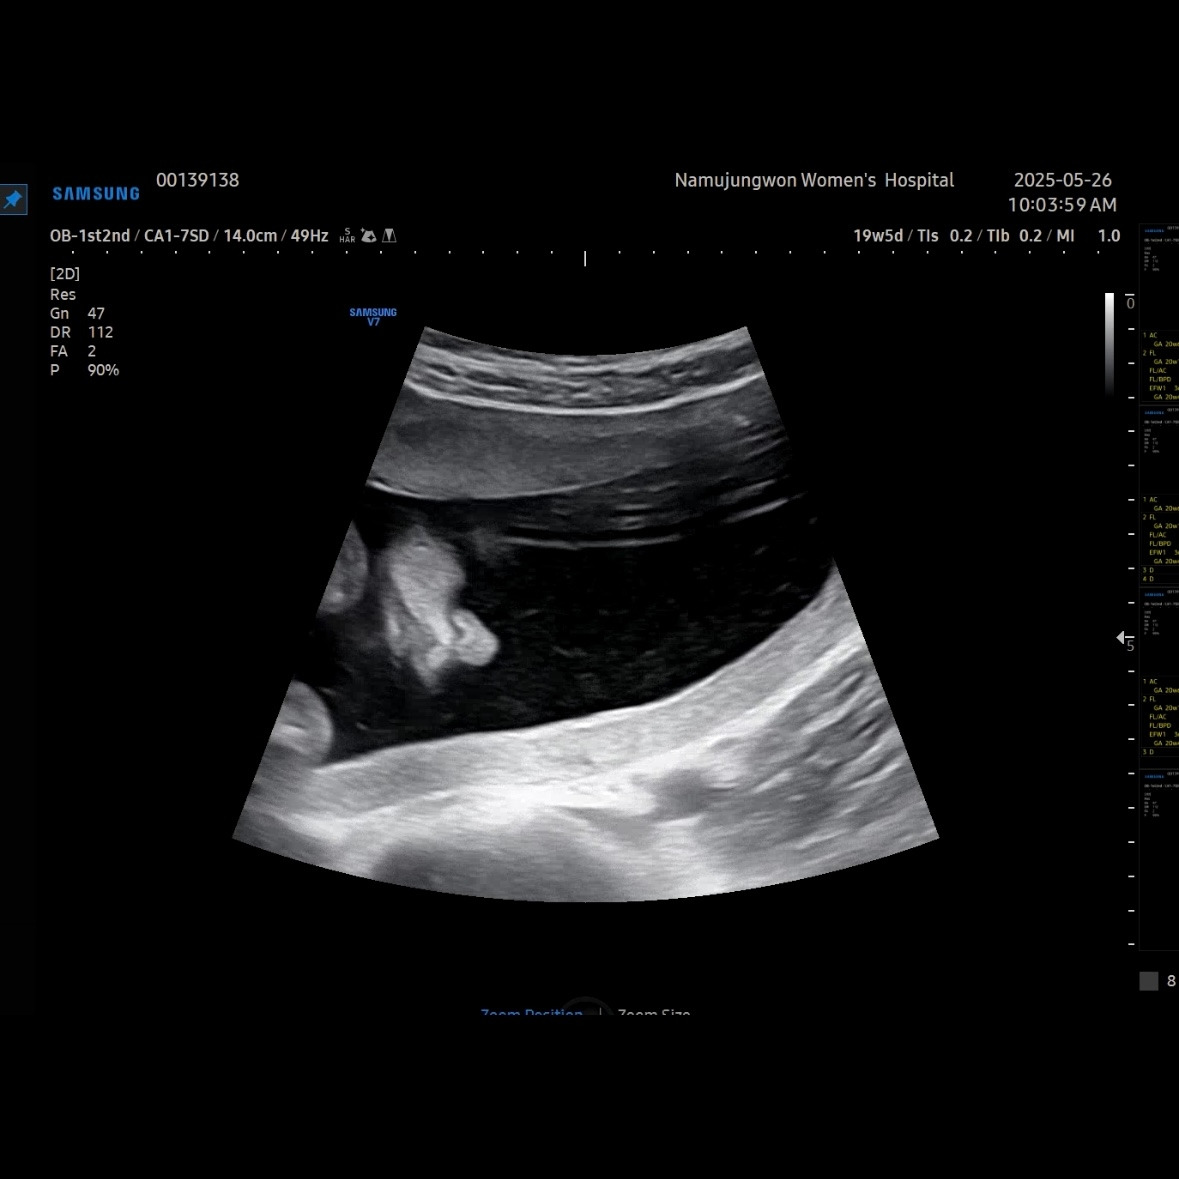

유민이 19주 5일 차에 보러 간 초음파

초음파를 보면 머리둘레, 배둘레, 허벅지 뼈길이를 꼭 재보는 데 유민이는 갈 때마다 1주 정도씩 평균보다 크게 측정된다. 1-2주 크기차이는 의미 없다고 괜찮다고 했다.

이제 얼굴이 형태가 많이 보인다. 코랑 입 위주로 보여줬다. 눈 쪽으로는 손을 올리고 있었다. 이렇게 보면 장기나 뇌나 얼굴이나 대부분 만들어져서 꽤 클 것 같이 생각되지만, 아직까지 400g이 안 되는 무게였다.